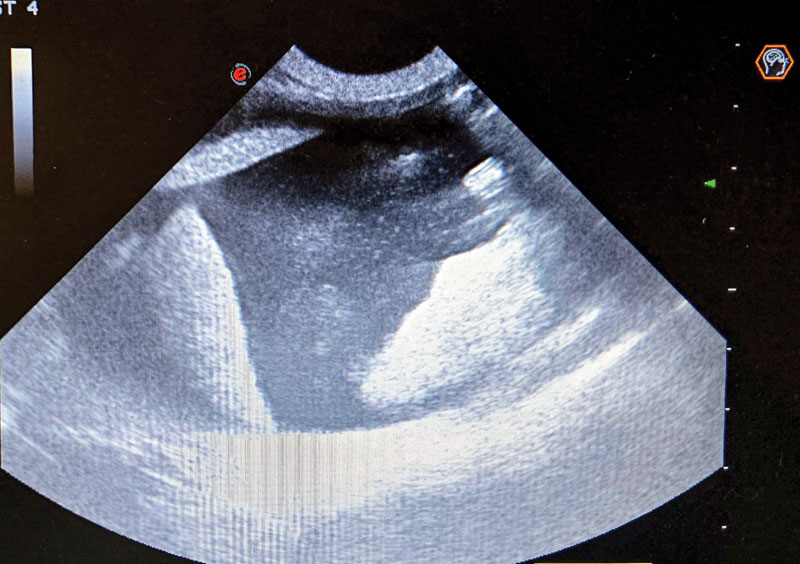

A 12-year-old M/N mixed breed presented for acute collapse, hemoabdomen with significant ascites.

3) Figure 3. This is an example of a classic hemoabdomen presentation. A large to giant breed dog collapses. It was fine the day prior and then acutely weak, lethargic, and ghostly white. This demonstrates the presence of a large volume of peritoneal fluid that, when aspirated, was consistent with a hemoabdomen.